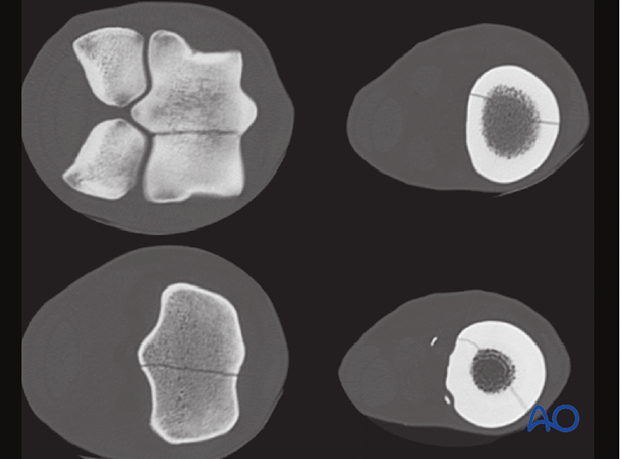

If surgical fixation under anesthesia is elected, the ideal way to assess these fractures is with a CT scan. This is by far the most accurate method of understanding the fracture configuration and planning a surgery.